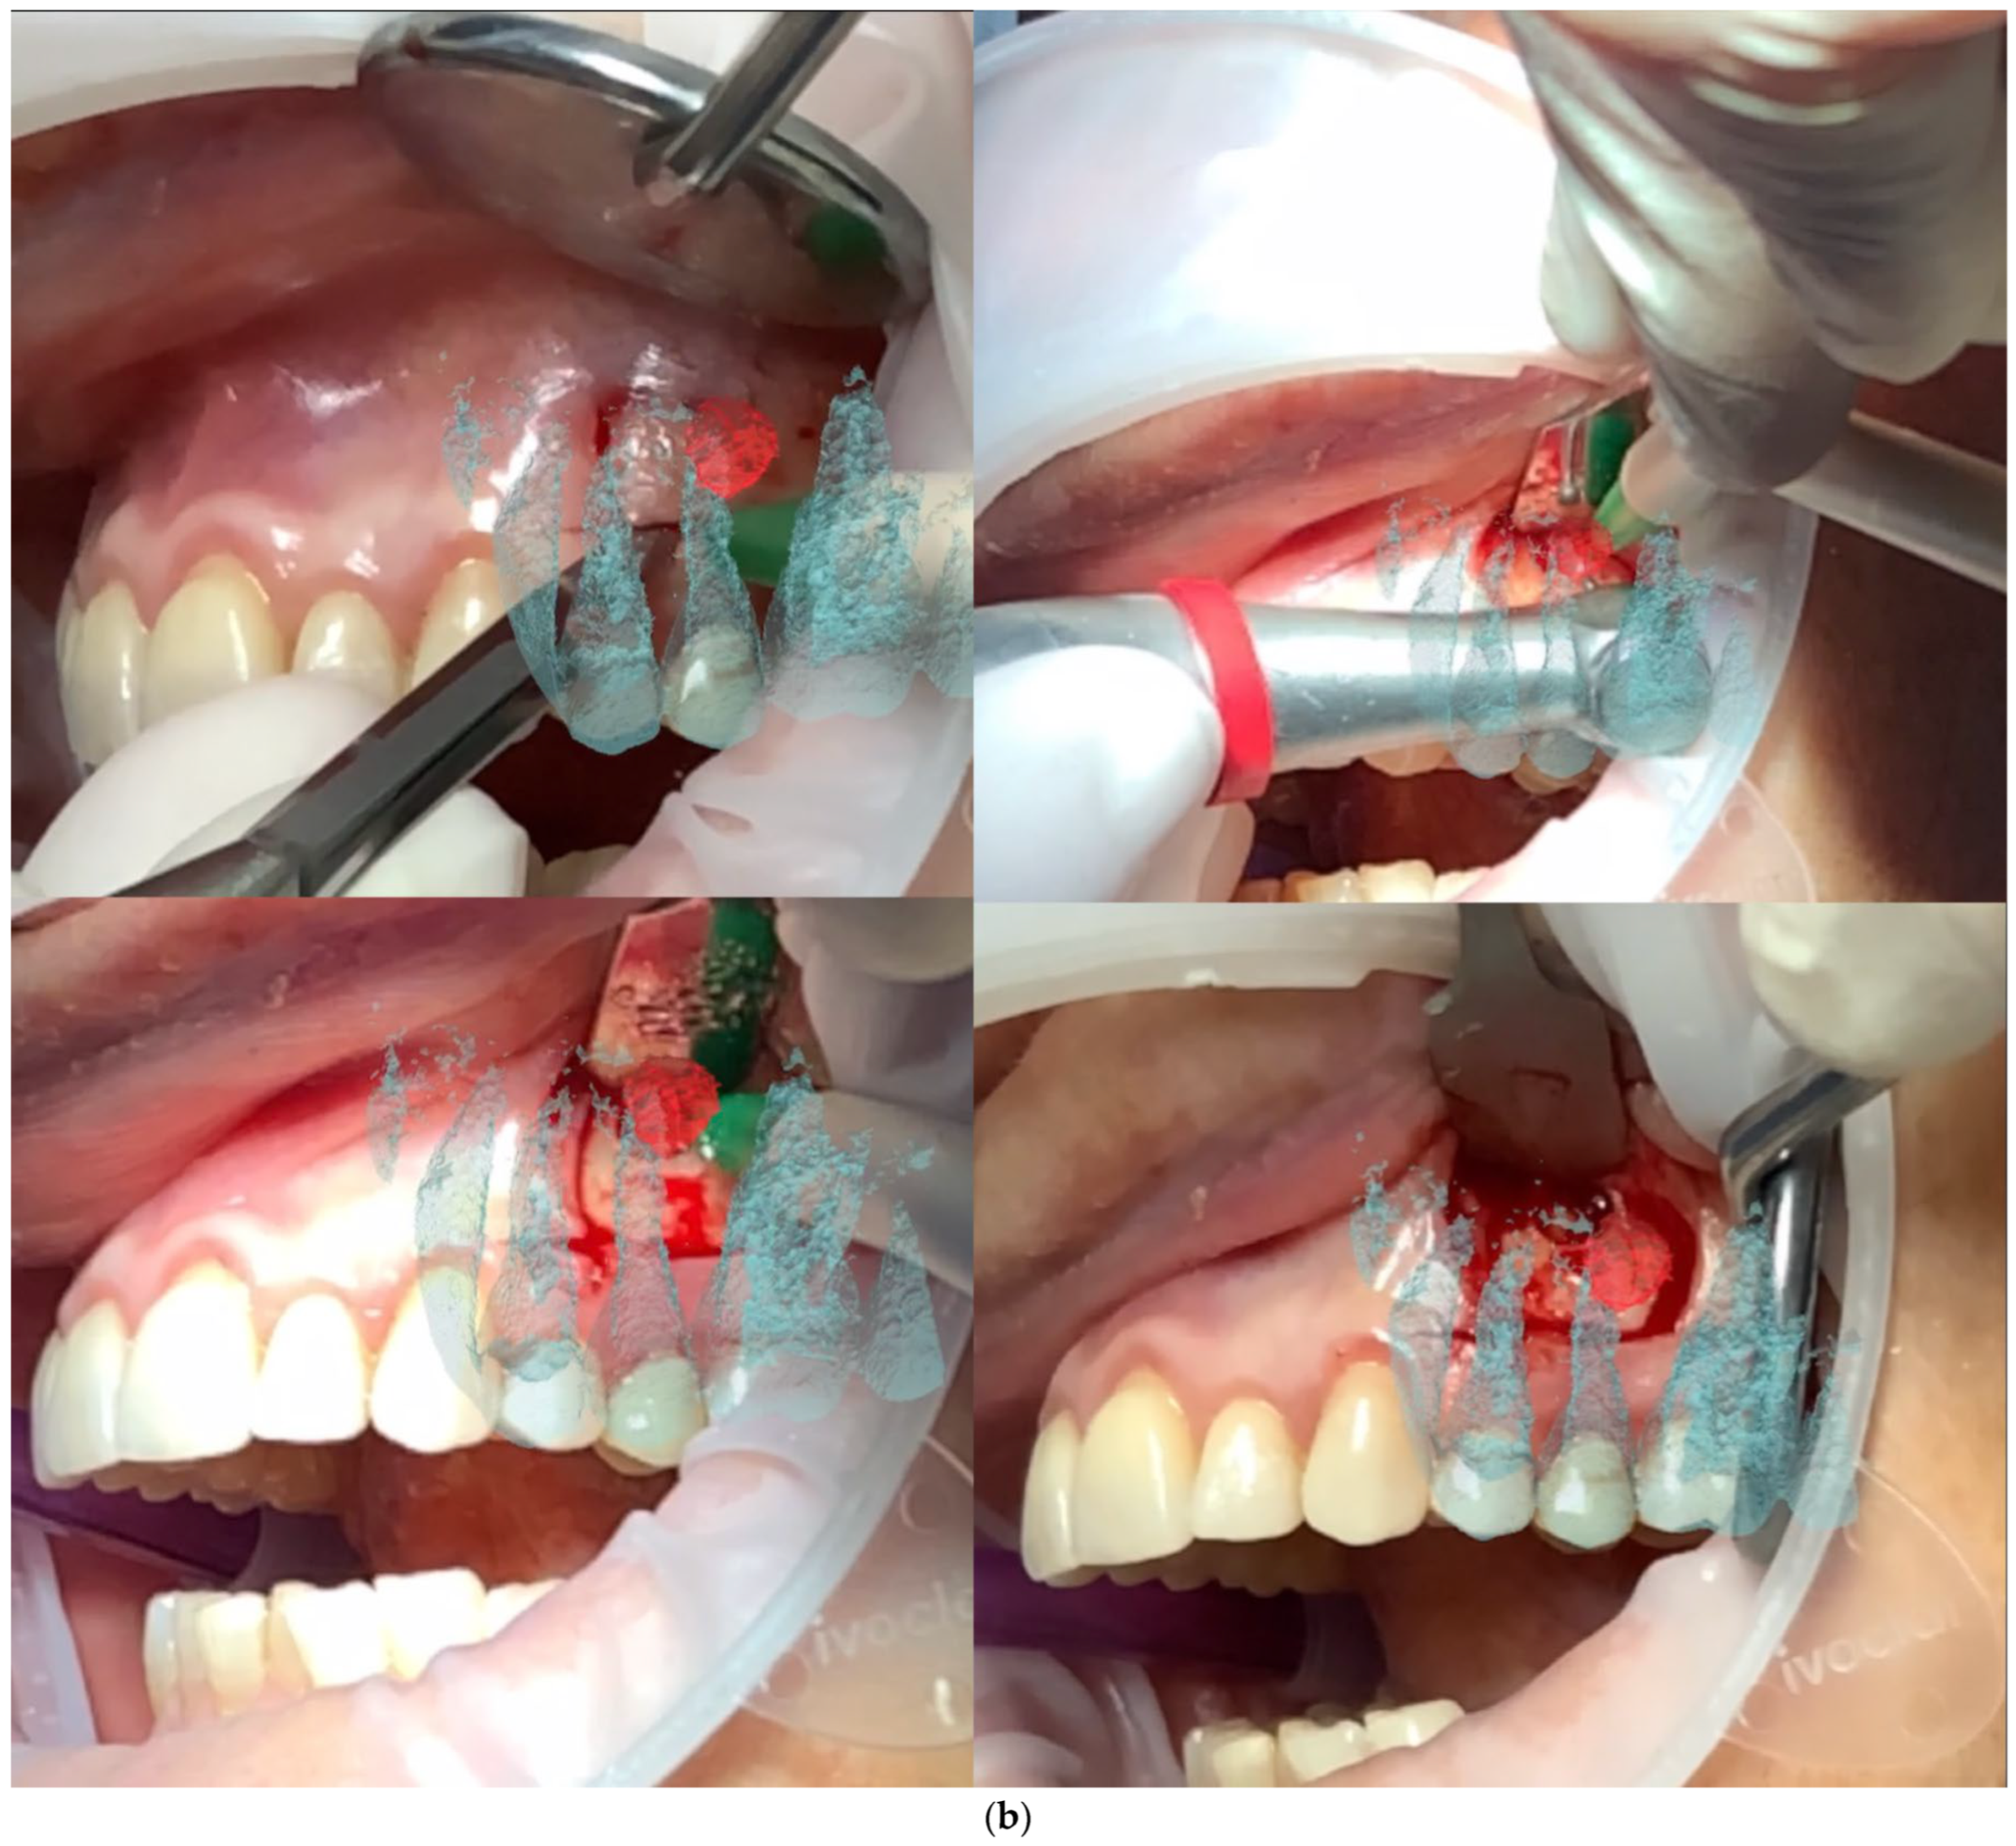

2.5. Surgical Procedure

All patients were treated under local anesthesia using (4% Articaine with Adrenaline 1:100,000 or 1:50,000 for better bleeding control). The iPad device was positioned in front of the surgical field, and the operator visualized the overlapped digital apex and root canal. The correct overlap was checked in the six degrees of freedom by rotating the device around the clinical scene in different projections (Figure 3 and Figure 4). A semilunar flap was elevated to expose the surgical site most proximal to the root’s apex according to the AR guide. The alveolar bone was carefully removed using a low-speed round bur under copious irrigation, guided by the superimposed 3D models. The root was resected at least 3 mm coronal to the apex to cut the apical portion of the root, with a buccal bevel, to grant clinical view and access. After the resection of the root, a blu methylene with a micro-brush was inserted into the surgery zone and over the cut root to highlight the contour of the root, the main and accessory canal for the retrograde preparation. In the meanwhile, minimal bone removal as well as a lack of trauma to the neighbour roots and apexes was ensured (Figure 5). The infra bony lesion was removed carefully, and the residual root was cleaned through courettes and an ultrasonic scaler. The retrograde preparation was carried out with ultrasonic diamond tips and a bioceramic root-end filling material was placed. The flap was sutured with 6–0 sutures, and a postoperative periapical rx was taken to confirm the resection margin and retrograde filling material location.

3. Results

All three patients completed the study without intraoperative or postoperative complications. The AR overlap required an average of [1.49 ± 0.34] min [Figure 3, Figure 4 and Figure 5]. The overall surgical time ranged between (27 and 42) min.

Figure 3. Overlap of the digital elements is checked in the six degrees of freedom by changing the orientation of the hand-held device (a). Intra-operative view with AR overlay guiding the phases of the inter-vention (b).